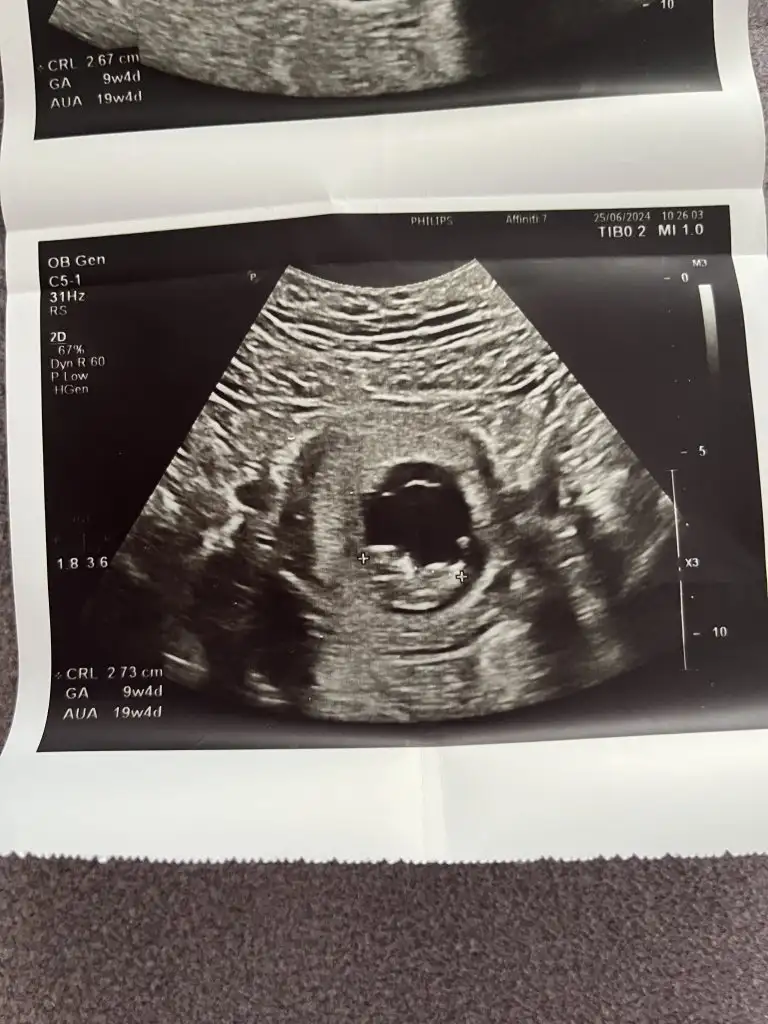

Azıcık anlıyorsam kız gibi geldi banaKızlar cinsiyet tahmini alabilir miyimbu arada 12 haftalık olduk

Yaaa maşallahKızlar cinsiyet tahmini alabilir miyimbu arada 12 haftalık olduk

Kızda da öyle çıkıntı görünüyor ama yere paralelse kız havaya dikse erkek diye biliyorumİlk resimdeki pipi değil mi yaney o peki

Evet hep orda yanılıyor anneler kız olunca dümdüz bişey görünecek sanılıyorYaaaaa ne bileyim bende onu ona benzettimdoktorum da kıza benziyor ama daha cinsiyet tahmini için erken dedi. Bende orada çıkıntı görünce dedim bu erkek heralde

Bana da bakar mısınız kızlar cinsiyet tahmini neye göre yapılıyor . Birde bebeğin kafası neresi şu çıkıntılar elleri mi ya anlamadım![]()